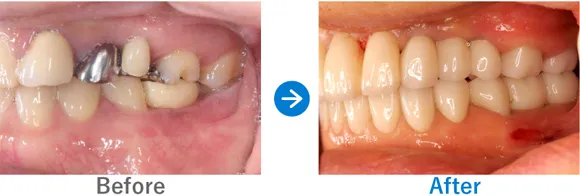

Case1

奥歯をインプラントに。ガイド&10年保証ありでコストパフォーマンス◎

左下6が破折して抜歯

インプラント1本:左下6

308,000円(内訳:インプラント1本(ネオデント)、ガイド、仮歯、保証10年)

来院の背景

右下の奥歯が破折したため、抜歯。インプラントを検討し来院されました。できるだけ見た目よく仕上げてほしいとのご要望もありました。

治療結果

骨の治癒がよく骨幅もあったため、骨造成をすることなくインプラント手術ができました。噛む力が強いため、今後は噛み締めや食いしばりによるインプラントへの負担を軽減していくことがポイントです。対策方法としては、マウスピースやボツリヌストキシン注射などがあります。また、定期的なメンテナンスも重要です。